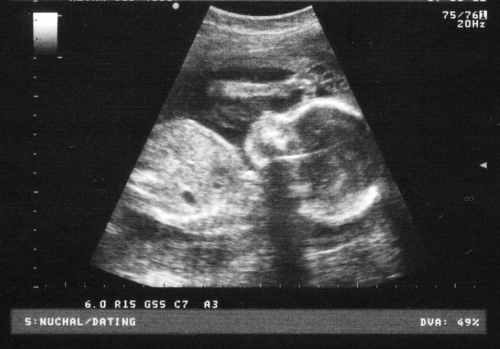

4 – Porém, confrontados nas últimas semanas com um caso concreto de uma menina de 12 anos, grávida, assistimos impotentes à mui questionável decisão de fazer abortar uma criança com mais de 22 semanas de gestação (como tudo indica, apesar de se ter dito sempre 5 meses…). Às 22 semanas já há viabilidade de nascimento com vida. Isto é, decidiu-se a morte de “um bebé já formado” – como diz o povo. Tal decisão, foi mais um passo dado no sentido da destruição, da violência e da falta de solidariedade. Claro que aquela vida trazia consigo dificuldades várias. Seriam intransponíveis? Na ponderação de valores, haverá algum valor superior a este (Vida)?